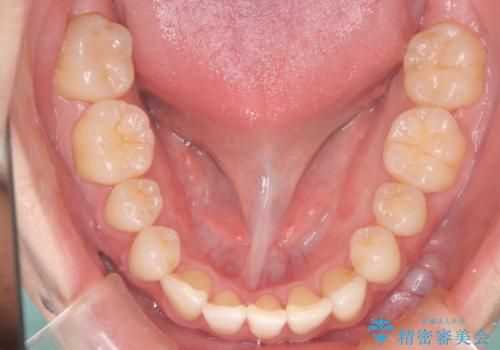

初診時の歯並びの状態としては、上下ともに前歯部の中等度のがたつきがあり、上の前歯が重なっている状態でした。

また元々下の前歯は1本少なく、歯の本数が少ないことを前提とした矯正治療を行いました。

抜歯は必要なく、マウスピース矯正にて治療を行っています。